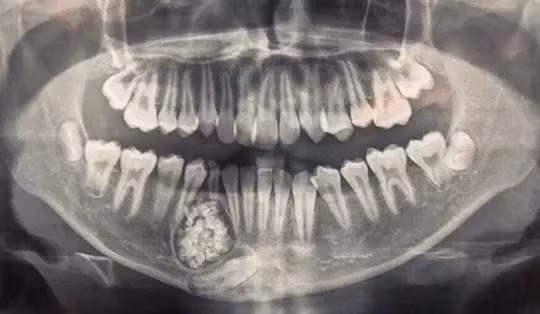

Ngày 15/6, bác sĩ Nguyễn Đức Tuấn, Trưởng khoa Răng Hàm Mặt, Bệnh viện Đa khoa tỉnh Khánh Hòa, thông tin các bác sĩ của đơn vị này phối hợp Bệnh viên Răng Hàm Mặt Trung ương TP.HCM phẫu thuật, lấy gần 100 cái răng trong khối u ở hàm dưới của bệnh nhân H.G. K. (13 tuổi, ngụ thành phố Nha Trang, tỉnh Khánh Hòa).

Những chiếc răng nhỏ có đầy đủ thân, tủy và chân răng.

U răng với gần 100 chiếc răng nhỏ. Ảnh: Bệnh viện Đa khoa Khánh Hòa cung cấp.

Qua chụp X-quang, các bác sĩ phát hiện một khối u răng ở xương hàm dưới.

Theo bác sĩ Tuấn, u răng (hay còn gọi Odontoma) là một trong những loại u lành tính. U răng rất khó phát hiện, chỉ qua phim chụp X-quang mới có thể nhìn thấy.